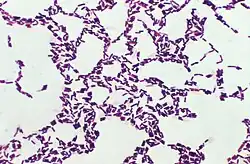

Bacillus es un género de bacterias en forma de bastón y gram positiva.[2] El género Bacillus pertenece al filo Bacillota. Son aerobios estrictos o anaerobios facultativos. En condiciones estresantes forman una endospora de situación central, que no deforma la estructura de la célula a diferencia de las endoesporas clostridiales. Dicha forma esporulada es resistente a las altas temperaturas y a los desinfectantes químicos corrientes.

Una manera fácil de aislar Bacillus es mediante la colocación de suelo no estéril, en un tubo de ensayo con agua, agitando y colocando en un fundido de sal de agar manitol, e incubando a temperatura ambiente durante al menos un día. Las colonias son generalmente de gran tamaño, extensión, y de forma irregular. Bajo el microscopio, las células Bacillus aparecen como barras, y una porción sustancial de las células por lo general contienen endosporas ovaladas en un extremo, por lo que es una protuberancia.